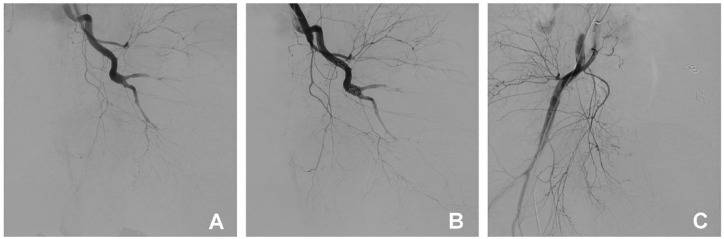

本病例报告详细描述了一名 45 岁男性建筑工人在高处坠落并随后与水泥搅拌机相撞后多处严重受伤的棘手治疗过程。患者出现大面积损伤,包括截肢、骨折和内出血,导致了被称为 "死亡三角 "的状态。尽管最初的预后很糟,ISS评分为28分,死亡风险系数高达89.56%,但通过多学科方法,病人还是被成功地抢救了过来。这包括损害控制复苏、紧急血管干预和有针对性的体温管理以保护大脑。病人的康复突显了综合创伤管理的有效性,以及协调护理在严重多发创伤病例中的关键作用。

This case report details the challenging management of a 45-year-old male construction worker who suffered severe multiple injuries after a fall and subsequent collision with cement mixers. The patient presented with extensive injuries, including amputation, fractures and internal bleeding, leading to a state known as the 'triangle of death'. Despite the initial grim prognosis, evidenced by an ISS score of 28 and a mortality risk coefficient of 89.56%, the patient was successfully resuscitated and managed through a multidisciplinary approach. This included damage control resuscitation, emergency vascular interventions and targeted temperature management for brain protection. The patient's recovery highlights the effectiveness of comprehensive trauma management and the critical role of coordinated care in severe multi-trauma cases.